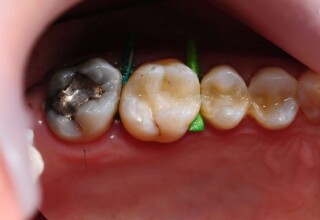

Αποκατάσταση Ραγισμένου Γομφίου με σφράγισμα Σύνθετης Ρητίνης

Τα ραγισμένα δόντια αποτελούν μια πρόκληση για την επανορθωτική οδοντιατρική από την άποψη της δυσκολίας της αποκατάστασης(συνήθως μεγάλα σφραγίσματα) άλλα κυρίως από τα προληπτικά μετρά που πρέπει να παρθούν για να αποφευχθεί ένα πλήρες κάταγμα. Η ακόλουθη περίπτωση παρουσιάζει την απλούστερη προσέγγιση της άμεσης συγκολλούμενης αποκατάστασης από σύνθετη ρητίνη. Βασίζεται στο σκεπτικό ενός συγκολούμμενου σφραγίσματος που «κρατάει» τα εναπομείναντα οδοντικά τμήματα «ενωμένα». Ο συγκεκριμένος γομφίος παρέμεινε ακέραιος για δυο χρονιά, οπότε χρειάστηκε απονεύρωση γιατί νεκρώθηκε και κατόπιν τοποθετήθηκε στεφάνη για αυξημένη προστασία.